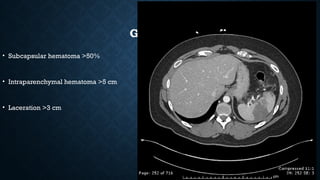

GRADE III

• Subcapsular hematoma >50%

• Intraparenchymal hematoma >5 cm

• Laceration >3 cm

GRADE III • Subcapsularhematoma >50% • Intraparenchymal hematoma >5 cm • Laceration >3 cm